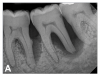

(6.) Initial periapical radiograph taken on November 15, 2015, showing infrabony defect approaching the apex of the distal root of tooth No. 19, on which there was a calcified mass (hypercementosis) and evidence of furcal bone loss. The entire distal root of tooth No. 18 appeared to have no bone support, and a small arrested carious lesion was noted on the distal crown of tooth No. 18. Teeth Nos. 17 and 18 were initially given a hopeless prognosis and slated for extraction.

Figure 6

A 63-year-old male patient with a medical history of asthma, hay fever, sinusitis, and arthritis was referred for periodontal therapy in November 2015. He reported taking multivitamins, fish oil, and naproxen sodium occasionally for pain. The patient did not report experiencing any dental discomfort. The clinical findings, radiographic interpretations, diagnosis, and preoperative prognosis for teeth Nos. 17 through 19 are summarized in Figure 6 and Table 1. The patient was informed that teeth Nos. 17 and 18 should be extracted and that tooth No. 19 would need regenerative therapy. A treatment plan was devised for phase I and phase III periodontal therapy, and the patient consented to the proposed treatment verbally and in writing.

(7.) Progressive improvement in bone quality, quantity, and morphology during each time period, especially in the furcation area of tooth No. 18, which shows a noticeable narrowing of the width of the bony defects, slight apical resorption of the distal root of tooth No. 18, and the encasing of residual cementum on the distal root of No. 19 by new bone formation. Periapical radiographs were taken of teeth Nos. 17, 18, and 19 on June 25, 2016, January 28, 2017, August 23, 2019, and September 4, 2020, respectively, the final of which was taken after almost 5 years post-initial scaling and root planing and alternating supportive periodontal maintenance.

(8.) Progressive improvement in bone quality, quantity, and morphology during each time period, especially in the furcation area of tooth No. 18, which shows a noticeable narrowing of the width of the bony defects, slight apical resorption of the distal root of tooth No. 18, and the encasing of residual cementum on the distal root of No. 19 by new bone formation. Periapical radiographs were taken of teeth Nos. 17, 18, and 19 on June 25, 2016, January 28, 2017, August 23, 2019, and September 4, 2020, respectively, the final of which was taken after almost 5 years post-initial scaling and root planing and alternating supportive periodontal maintenance.

Figure 8

(9.) Progressive improvement in bone quality, quantity, and morphology during each time period, especially in the furcation area of tooth No. 18, which shows a noticeable narrowing of the width of the bony defects, slight apical resorption of the distal root of tooth No. 18, and the encasing of residual cementum on the distal root of No. 19 by new bone formation. Periapical radiographs were taken of teeth Nos. 17, 18, and 19 on June 25, 2016, January 28, 2017, August 23, 2019, and September 4, 2020, respectively, the final of which was taken after almost 5 years post-initial scaling and root planing and alternating supportive periodontal maintenance.

Figure 9

(10.) Progressive improvement in bone quality, quantity, and morphology during each time period, especially in the furcation area of tooth No. 18, which shows a noticeable narrowing of the width of the bony defects, slight apical resorption of the distal root of tooth No. 18, and the encasing of residual cementum on the distal root of No. 19 by new bone formation. Periapical radiographs were taken of teeth Nos. 17, 18, and 19 on June 25, 2016, January 28, 2017, August 23, 2019, and September 4, 2020, respectively, the final of which was taken after almost 5 years post-initial scaling and root planing and alternating supportive periodontal maintenance.

Figure 10